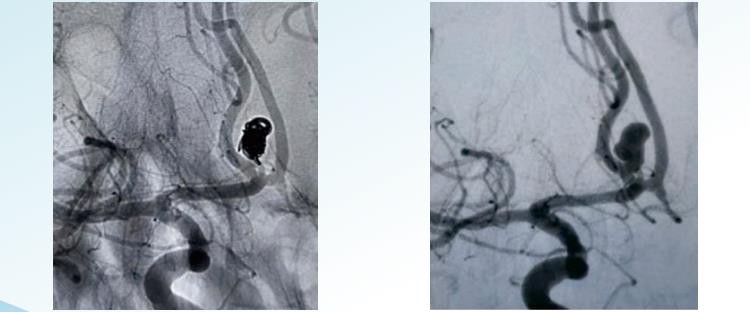

رینوواٹی ایمڈیٹیک ایبل انوریزم کوئیلنگ سسٹم 1 سے 22 میٹر تک قطر میں اینڈوواسکولر ایمبولائزیشن کے لئے بے ترتیب ، ہیلیکل اور 3D علیحدہ اختیارات پیش کرتا ہے۔ یہ فریم سے ختم ہونے تک aneurysms کو متحرک کرنے کے لئے ڈیزائن کیا گیا ہے اور اس میں خاص طور پر کنڈلی کی شکل والی کنڈلی شامل ہے جس میں اعلی پیکنگ کثافت کو حاصل کرنے کے ل concent کنسٹرک انیورزم فلنگ اور بڑے حجم کے کنڈلیوں کو حاصل کیا جاسکتا ہے۔ بے ترتیب کوئلنگ انوریزم کوئنگ تکنیک کی آسان اور قدیم ترین شکل ہے۔ اس میں ایک ہی کنڈلی یا کنڈلیوں کے ایک گروپ کو انوریزم میں داخل کرنا شامل ہے۔ کنڈلی عام طور پر پلاٹینم سے بنی ہوتی ہیں اور پتلی اور مضبوطی سے کنڈلی ہوتی ہیں تاکہ کسی بھی خلا یا خالی جگہوں کو تھیلی میں بننے سے بچایا جاسکے۔ ہیلیکل کوئنگ میں ایک لمبی ، پتلی تار کا استعمال شامل ہے جو خود کو ہیلیکل انداز میں گھیرے ہوئے ہے ، جس سے ایک بہار - تشکیل ہوتا ہے جیسے ڈھانچہ۔ تار کو سیدھے ہوئے شکل میں اینوریسم میں داخل کیا جاتا ہے ، اور ایک بار اندر ، اس کو انوریزم تھیلی کو بھرنے کے لئے کنڈلی اور وسعت دینے کی اجازت دی جاتی ہے۔ ہیلیکل کنڈلی بے ترتیب کنڈلیوں کے مقابلے میں وسیع تر اور زیادہ قریب سے بھری ہوئی ہیں ، اس طرح انوریمزم کی بہتر موجودگی فراہم کرتی ہے۔ تھری ڈی کنڈلی میں ایک کسٹم - ڈیزائن کردہ کنڈلی کا استعمال شامل ہے ، جو کمپیوٹرائزڈ امیجنگ عمل کا استعمال کرتے ہوئے بنایا گیا ہے جو عین مطابق تین - جہتی ماڈل پیدا کرتا ہے۔ کنڈلی انوریمزم کے عین مطابق سائز اور شکل سے ملنے کے لئے تیار کی گئی ہے۔ اس قسم کی کنڈلی کو انیوریزم تھیلی میں سنجیدگی سے فٹ کرنے کے لئے ڈیزائن کیا گیا ہے ، جس سے بہترین موجودگی مہیا ہوتی ہے اور پیچیدگیوں کے خطرے کو کم کیا جاتا ہے۔

رینوواٹی ایم3D علیحدہ کنڈلی

رینوواٹی ایمہیلیکل علیحدہ کنڈلی